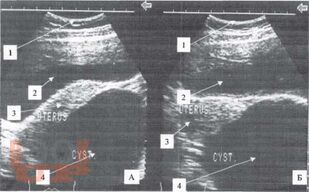

Томографическая диагностика опухолей и опухолевидных образований яичника у девочек

Диагностика и лечение опухолей и опухолевидных образований яичников у девочек и подростков является актуальной проблемой. Совершенство методов диагностики при данной патологии, хорошо зарекомендовавших себя во многих областях медицины, способствует внедрению их в клинику детской гинекологии, онкогематологии, детской хирургии.

Разнообразие средств диагностики, отличающихся по физическим данным и разрешающим способностям, а также по стоимости аппаратуры и самих исследований, часто ставит врача перед сложной проблемой определения необходимого минимума применяемых методов, последовательностью их выполнения и интегрирования результатов разных исследований в единую диагностическую концепцию.